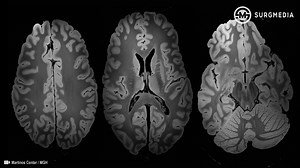

Mayo Clinic 7-Tesla MRI scanner i…